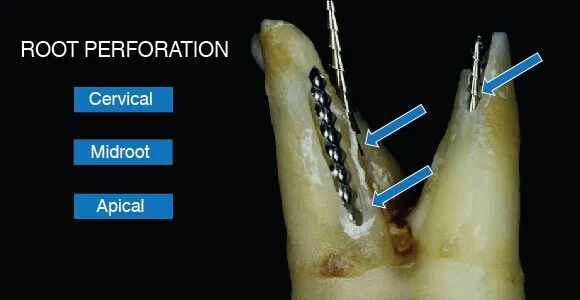

This category involves ledge formation, cervical, mid-root, or apical perforations, instrument separation, and canal blockage.